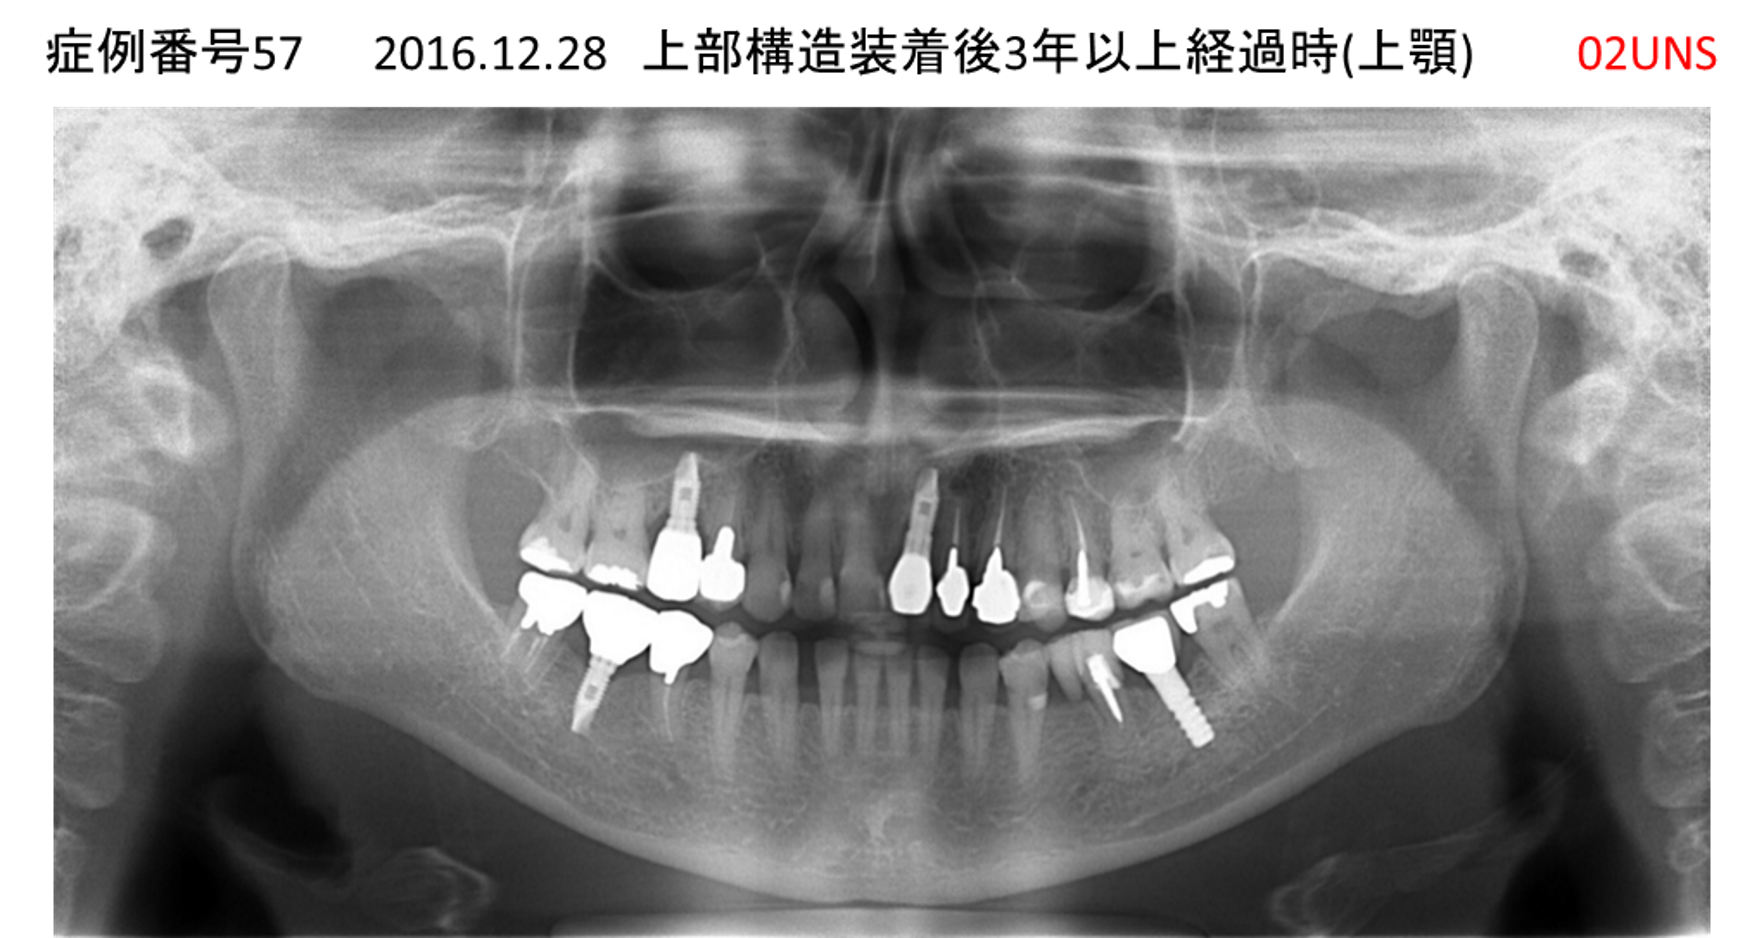

ご飯を美味しく食べたい/人前で笑えるようになりたい患者様のインプラント症例

| 治療名称 |

インプラント |

| 治療費用 |

480万円+税 |

| 治療期間 |

6か月 |

| 患者さんの症状(主訴) |

おいしいご飯が食べられるようになりたい 人前で笑えるようになりたい |

| 治療内容 |

サイナスリフト 抜歯即時インプラント |

| 治療結果 |

何でも食べられるようになった 人前で大口を開けて笑えるようになった |

| 治療の注意点(リスク/副作用) |

インプラントが壊れた場合は再治療が必要 |